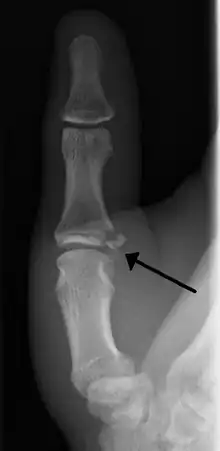

| Avulsion fractures of the ulnar base of the proximal phalanx of the thumb ( Gamekeeper's fracture ) | |

- Avulsion of distal UCL causing the pulling off of a bone chip off the proximal phalanx base.[3]

When approaching this type of injury, the physician must first determine whether there is an incomplete rupture (or sprain) of the UCL, or a complete rupture. If the UCL is completely disrupted, the physician must then determine whether there is interposition of the adductor aponeurosis (Stener lesion), or simply a complete rupture of the UCL with anatomic or near-anatomic position. Radiographs are helpful in determining the possible presence of an avulsion fracture of the proximal phalanx insertion site of the ulnar collateral ligament. Stress examination, or one done under fluoroscopic guidance, can help determine the integrity of the ligament.